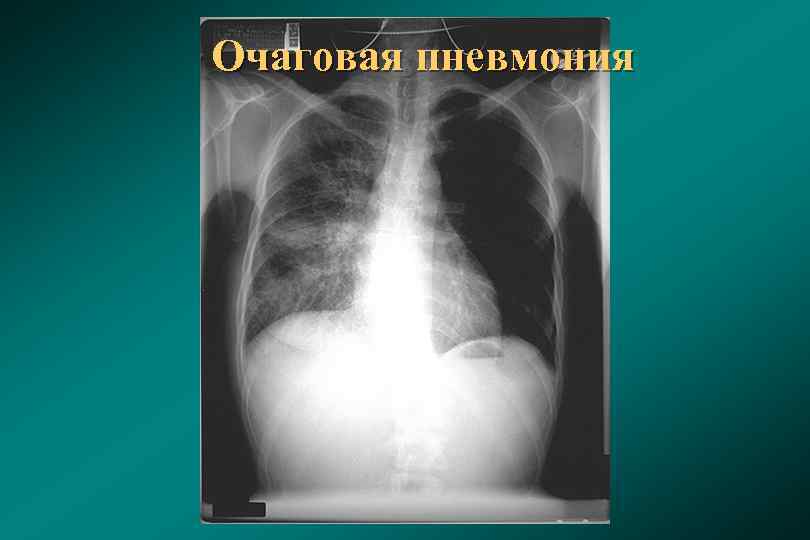

Рентгенодиагностика бронхопневмонии: Советы и примеры